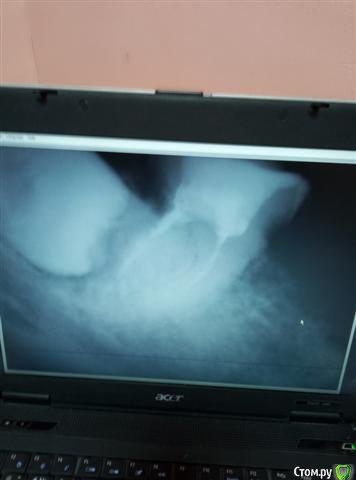

vlada77-77 Опубликовано 26 октября, 2019 Поделиться Опубликовано 26 октября, 2019 Здравствуйте! На рентгене обнаружили ретинированную восьмерку справа внизу.Мнения врачей разделились по поводу удаления.Один сказал срочно удалять и что там идет воспаление между 7 и 8 зубом,и что 7-й тоже нужно перелечивать. Другой врач сказал,что удалять не надо.Подскажите,нужно ли удалять ее или нет?И нужно ли перелечивать 7-й зуб? Ссылка на комментарий

Irouil Опубликовано 26 октября, 2019 Поделиться Опубликовано 26 октября, 2019 Вероятнее всего удалять я бы не рекомендовал, но на это снимке не виден практически один из корней семёрки соседней, так что попробуйте какой-то снимок покачественнее предоставить 1 Ссылка на комментарий

колесников Опубликовано 28 октября, 2019 Поделиться Опубликовано 28 октября, 2019 Это не воспаление. Эмаль зуба с костной тканью не срастается,коронка находится как бы в капсуле,ее мы и видим на снимке. Срочности в удалении нет. По поводу 7ки ничего определенного нельзя сказать,снимок малоинформативен. Ее нужно разобрать под коронку Ссылка на комментарий